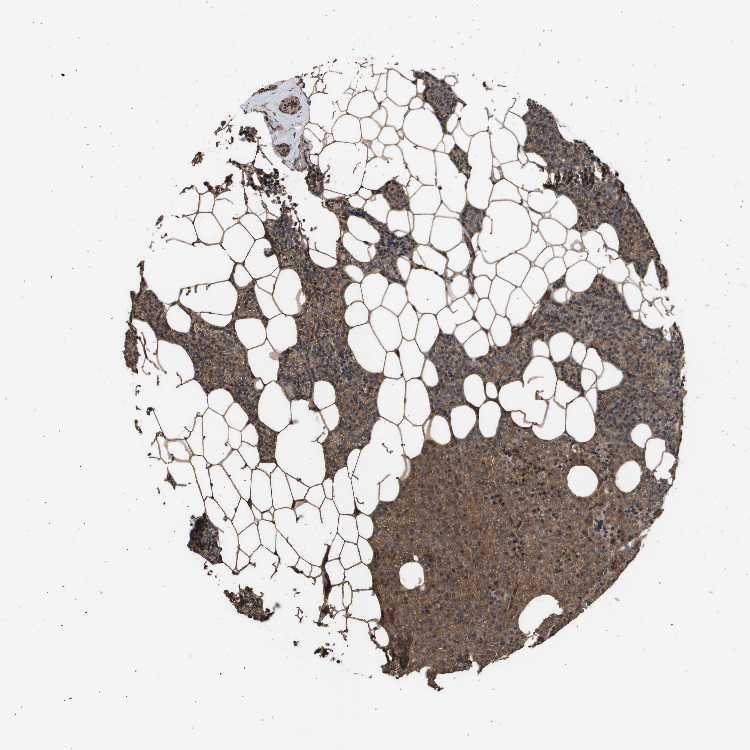

PARATHYROID GLAND - Antibody stainingi

Antibody staining in the annotated cell types in the current human tissue is reported as not detected, low, medium, or high, based on conventional immunohistochemistry profiling in selected tissues. This score is based on the combination of the staining intensity and fraction of stained cells.

Each image is clickable and will lead to virtual microscopy that enables deeper exploration of all samples and also displays staining intensity scores, fraction scores and subcellular localization as well as patient and tissue information for each sample.

Antibody HPA002185Antibody CAB017787

Glandular cells HighHigh